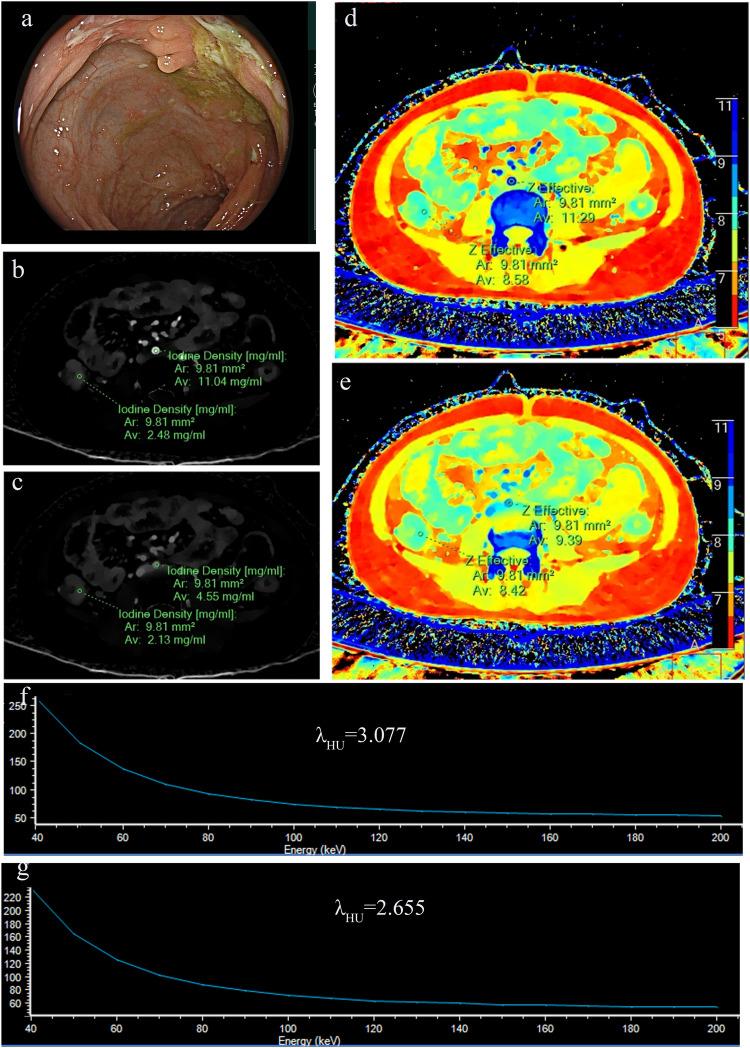

There were 110 active and 92 inactive bowel segments. In univariate analysis, the slope of spectral curve in the venous phases (λ-V) has the best diagnostic performance, with an area under the ROC curve (AUC) of 0.81 and an optimal threshold of 1.975. In the testing set, the AUC of the three models established by the 7 variables to differentiate CD activity was 0.81-0.87 (DeLong test p value was 0.071-0.766, p > 0.05), and the combined model had the highest AUC of 0.87 (95% confidence interval (CI): 0.779-0.959).

有110个活动肠段和92个非活动肠段。单因素分析中,静脉期光谱曲线斜率(λ-V)具有最佳诊断性能,ROC曲线下面积(AUC)为0.81,最佳阈值为1.975。在测试集中,由7个变量建立的用于区分CD活动度的3个模型的AUC为0.81-0.87(德龙检验p值为0.071-0.766,p>0.05),联合模型的AUC最高,为0.87(95%置信区间(CI):0.779-0.959)。